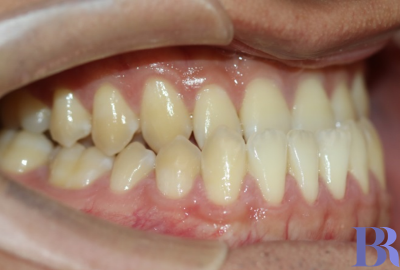

초진 입안사진입니다

치아가 거꾸로 물리고 있으나

실제 골격이 나온것에 비해서는

덜 나와 보이네요.

양악수술 대상자의 전형적인

치아 상태를 볼수 있습니다.

치성보상작용으로 인해

실제 골격에 비해 치아 간격이

좁아 보입니다

아랫니와 윗니 앞뒤 차이가

외모에 비해 심하지는 않습니다